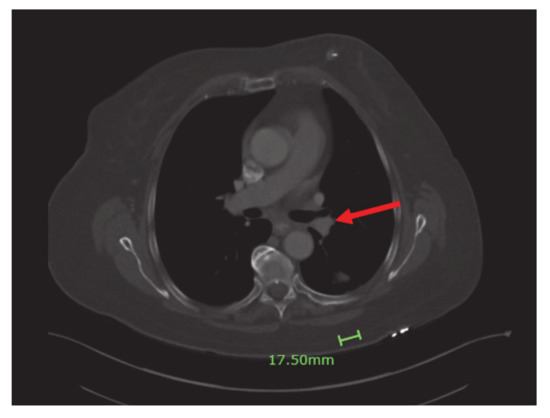

Four months into the treatment, the patient had a repeat CT scan done, which showed marked regression of the left lower lobe bronchial tumor (Figure 4) and re-expansion of the left lower lobe. The patient had been responding well to dabrafenib and trametinib. She continued with both agents with minimal side effects.

Figure 4.

Significant regression of the left lower lobe bronchial tumor (red arrow) and re-expansion of left lower love.